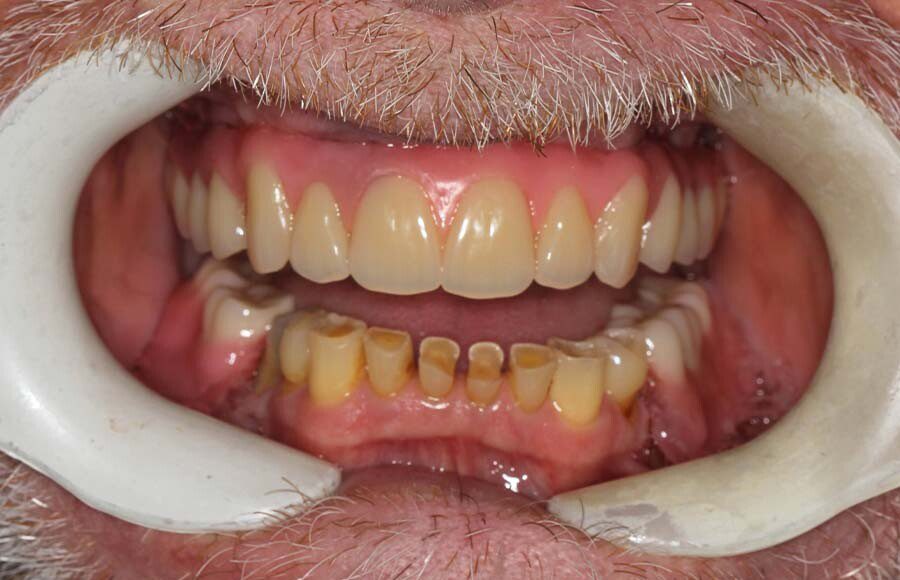

Frontal view of upper implant bridge (intra-oral). Just because the patient is delaying treatment on the lower doesn’t mean we can’t improve it for the year he is waiting. See next picture.

The lower teeth were bonded with composite resin to improve aesthetics and function during the year he is waiting to do his lower.

Smile of upper permanent and lower bonded teeth. The patient is starting to learn how to smile, again!